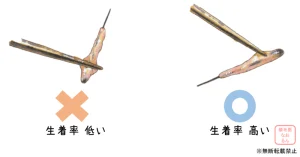

今回は、FUE法における使用機器の中でも、毛包を採取するためのパンチブレードについてお話ししようと思います。 パンチがないとグラフト採取ができないため、自毛植毛手術を行う医師にとっては無くてはならないものとなります。 植 […]

連日、2000Gを超える手術が続きました。移植の株数が多くなればなるほど、手術の難易度が増し、我々医師だけでなく、移植看護師の経験や実力がものを言います。 さて、本日はその大事な移植看護師の実力や質について、たくさんの看 […]